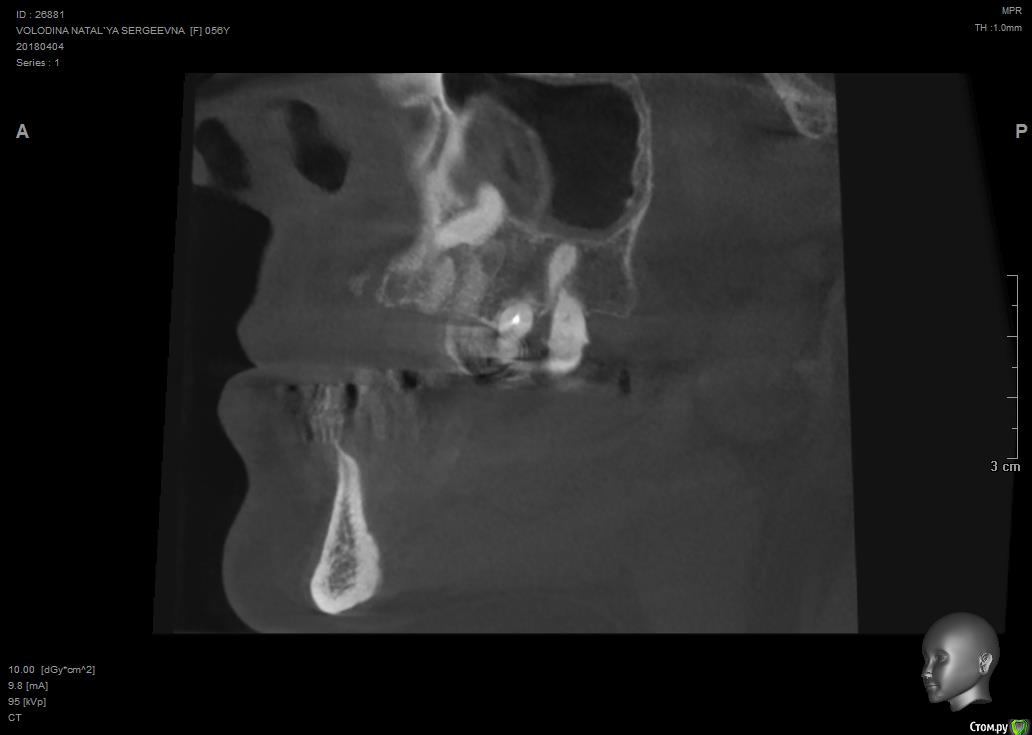

Павел7809 Опубликовано 9 апреля, 2018 Поделиться Опубликовано 9 апреля, 2018 Собственно ситуация такая. Предстоит каким то образом удалить ретенированный клык. Находится в небе, да и еще кривым апексом который торчит в носу. Полгода назад этому же пациенту почти такой же клык я удалил, но там как то все проще было по топографии. Собственно , господа, как и чем? Возможны ли какие то кровотечения носовые и тд. Кто сталкивался? Может как то распилить его со стороны щеки пополам и вытащить.. Ссылка на комментарий

Павел7809 Опубликовано 9 апреля, 2018 Автор Поделиться Опубликовано 9 апреля, 2018 Может так получше. Орто нет... Ссылка на комментарий

Павел7809 Опубликовано 9 апреля, 2018 Автор Поделиться Опубликовано 9 апреля, 2018 Так все тоже самое:Анестезия.Разрез.Декоронация.Удаление корня.Кюретаж.Швы.В нос провалитесь - плохо, но не страшно, будет кровать, тампонада носового хода.Я ведь правильно понимаю - сначала надо будет отрезать крючек со стороны щеки, сделав к нему окошко на уровне апексов 6 ки а потом удалить все остальное через небный доступ? Ссылка на комментарий

Борис80 Опубликовано 10 апреля, 2018 Поделиться Опубликовано 10 апреля, 2018 я бы вестибулярно делал, окно в области коронковой части, чуть апикальнее может, коронку отпилил, корень вывихнул Ссылка на комментарий